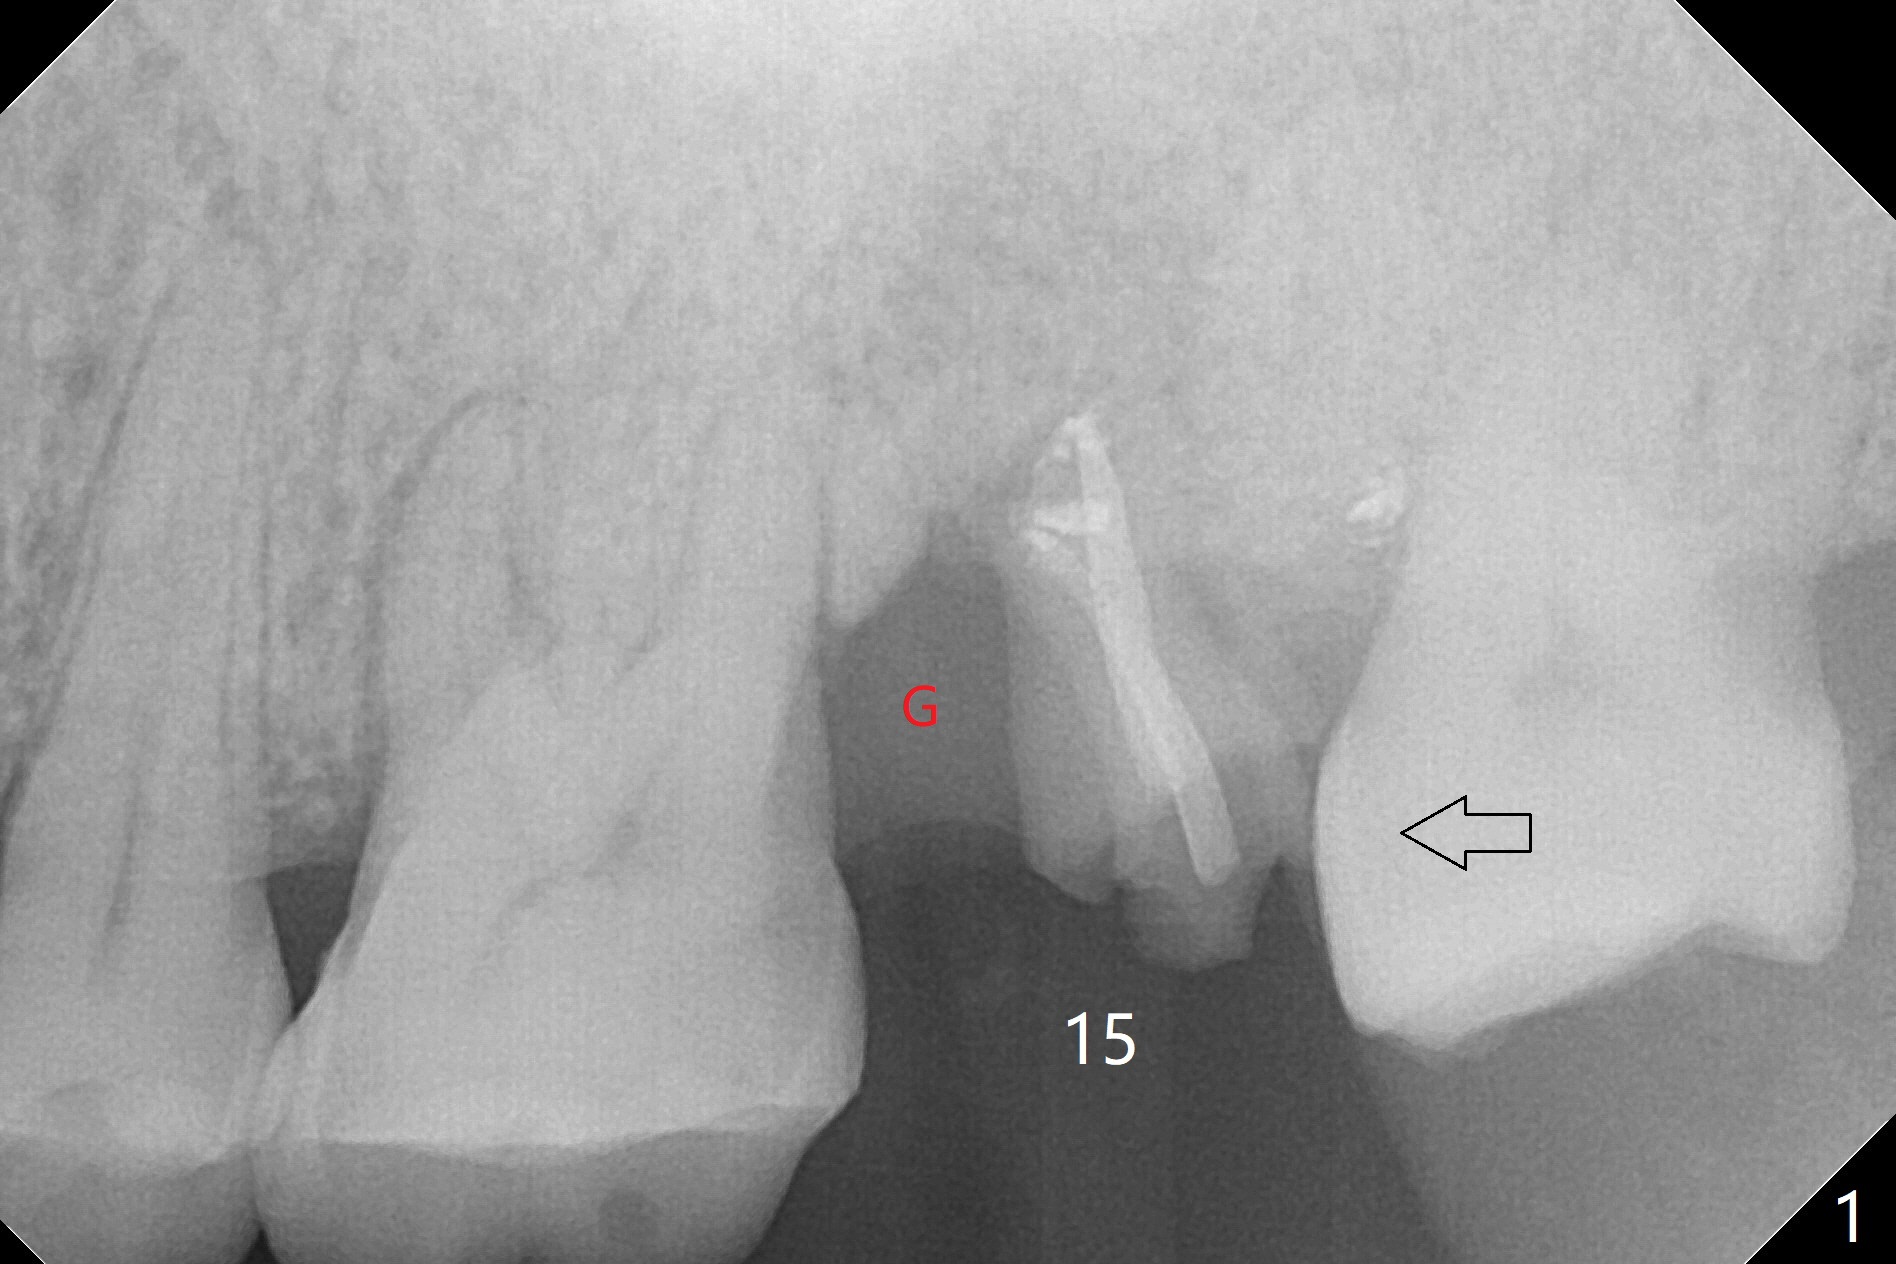

When the patient returns for the tooth #15 extraction and implant, the mesiobuccal residual root has been expelled, while the distobuccal and palatal roots seem to have extruded (Fig.1). The mesial portion of the gingiva (G) is intact and thick. The trajectory of the initial osteotomy is to be changed as shown by red line in Fig.2. The 3.8 mm drill appears to be distal (Fig.3). With mesial bone removal with Lindamann bur, the position of the final implant (5x13 mm) is within normal limit (Fig.4 (50 Ncm)). Because of the thick mesial gingiva (Fig.4 G) and placement of the 5.5x4(2) mm abutment, insertion of mixture of autogenous and Vanilla Graft (*) into the mesial aspect of the implant is difficult (Fig.4 >). Further pushing of the bone graft from the buccal and palatal socket gaps results in more ideal packing (Fig.5 >). If the bone graft were placed first, packing would have been easier. An immediate provisional is fabricated to prevent further mesial shifting of the 3rd molar (Fig.1 arrow). The implant remains stable, while the provisional and abutment are loose 3 months 1 week postop (Fig.6). Impression is taken after abutment cleaning and retightening. Because of the long implant (13 mm), a permanent crown can be cemented early (3 months 20 days postop, Fig.7).